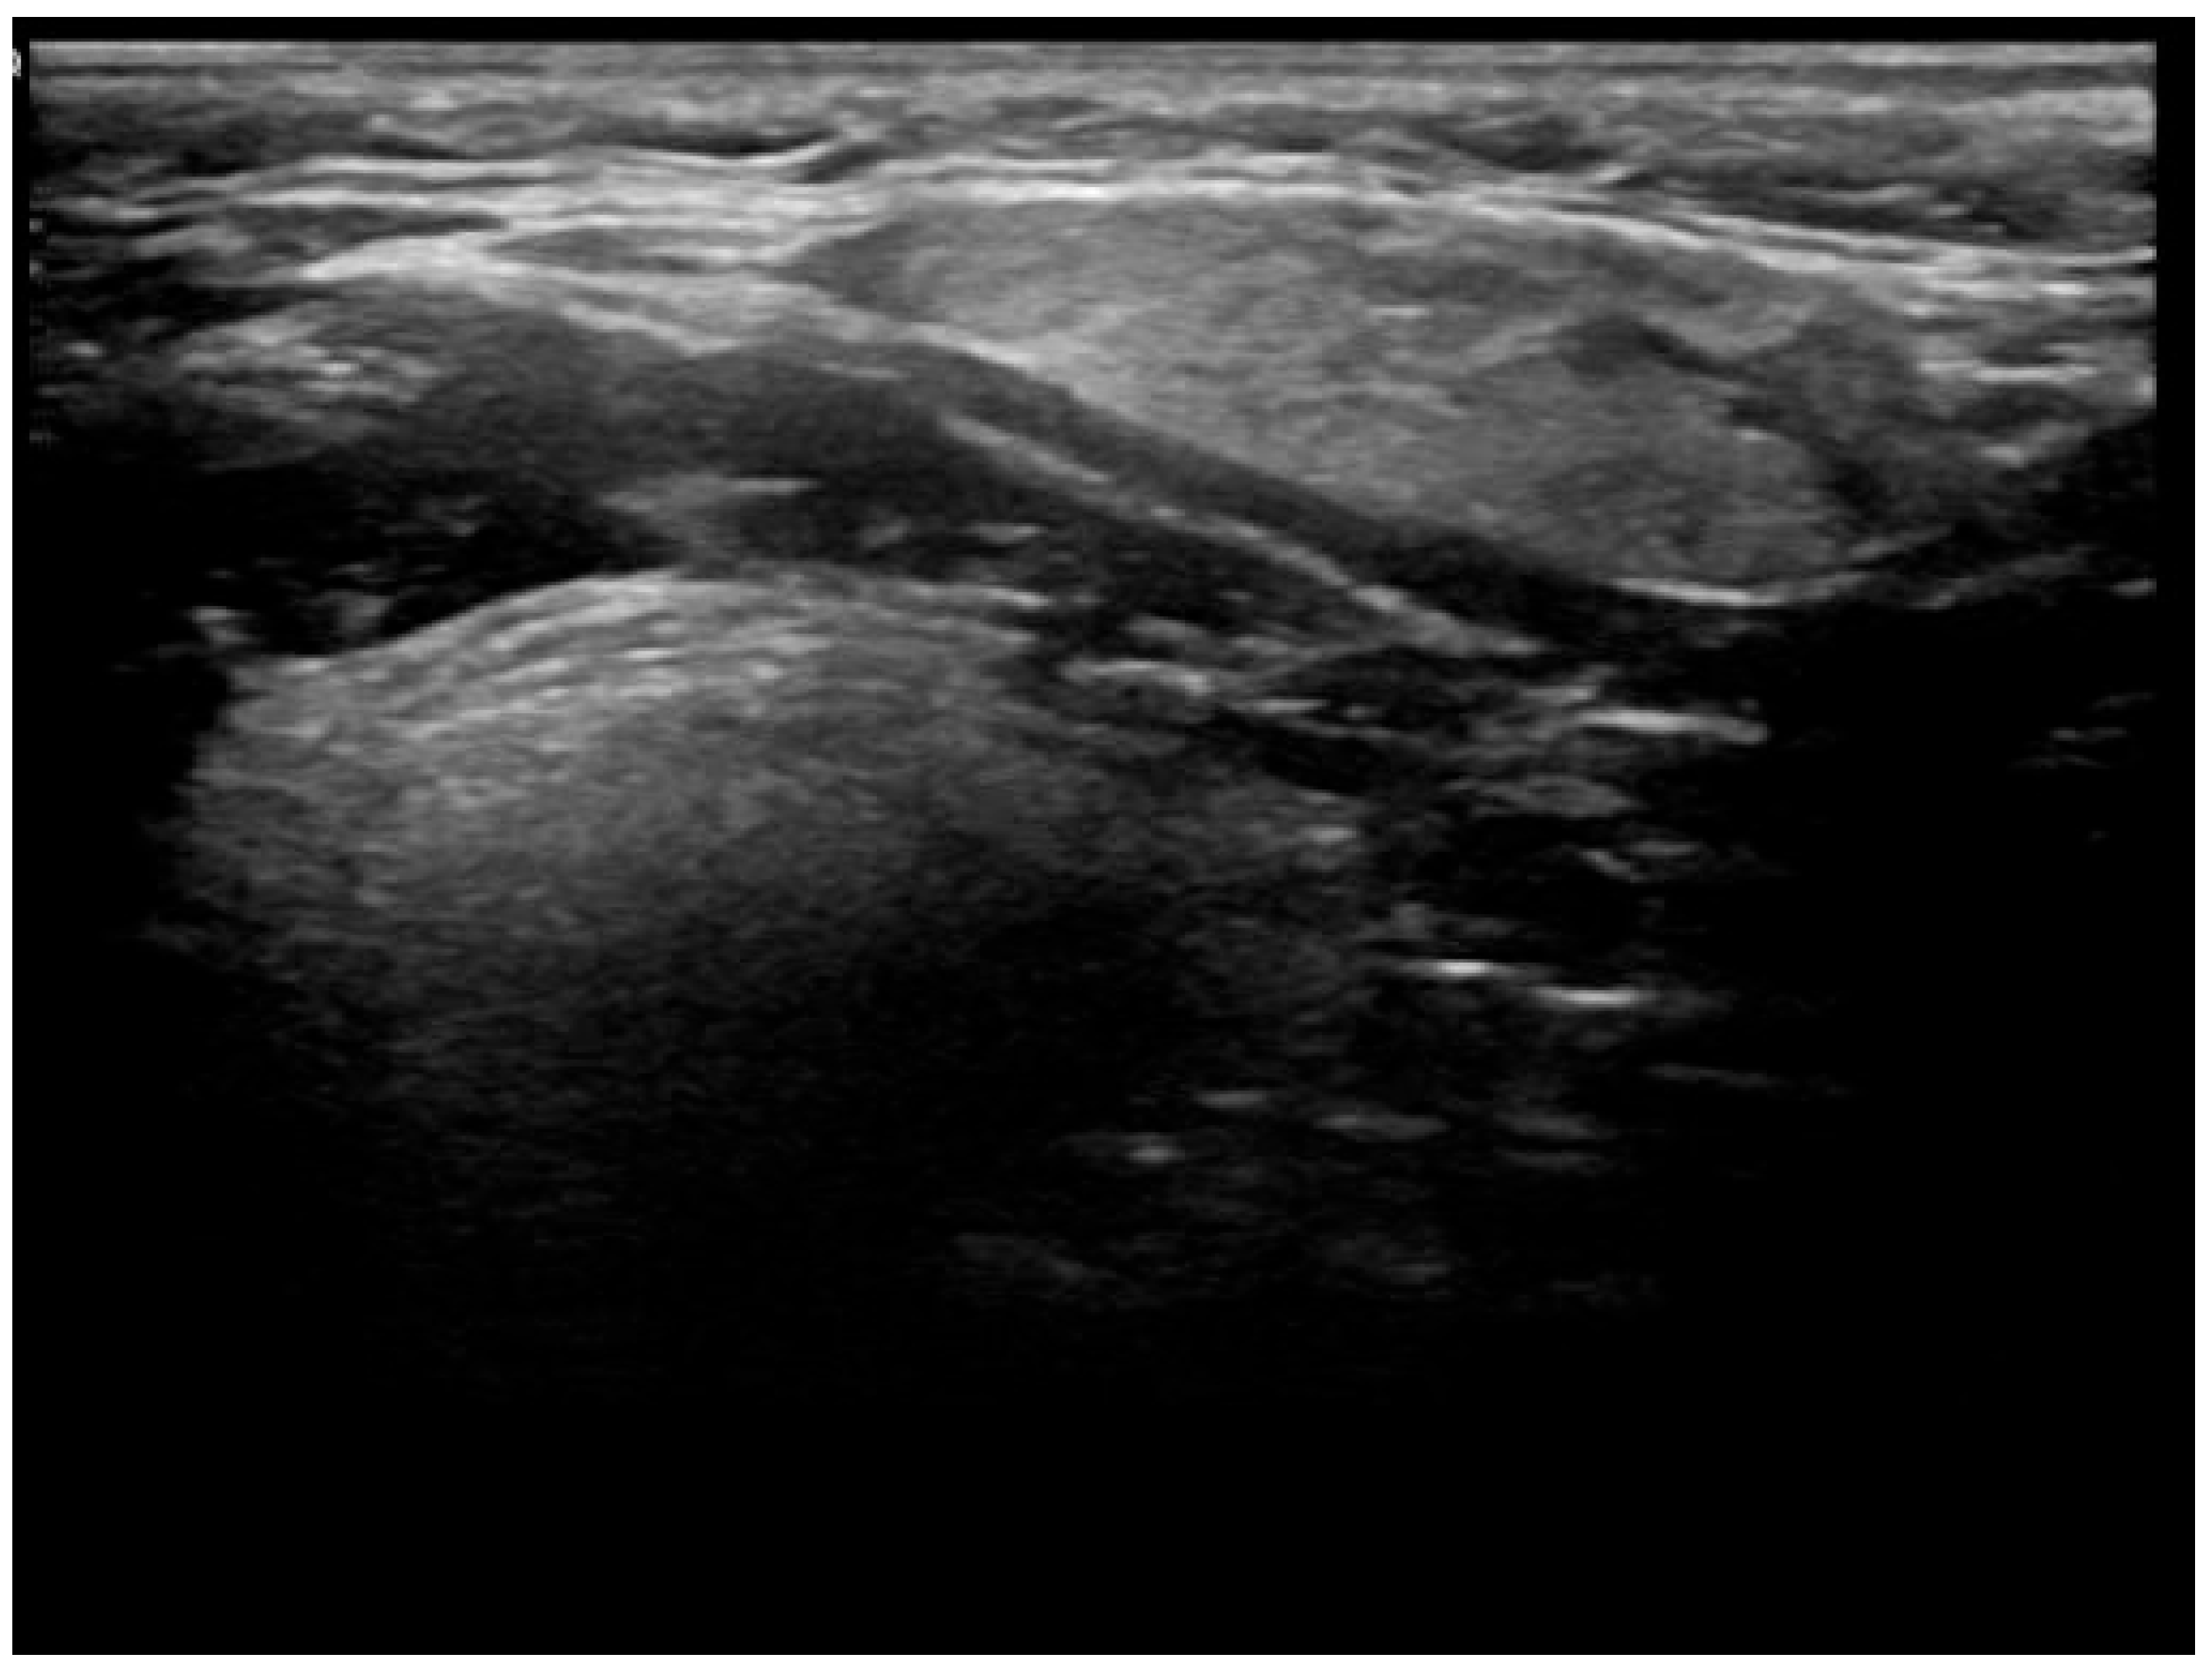

- Well-demarcated geographical area of low echogenicity with increased vascularity;

- Mild focal intrinsic duct dilatation within the SMG;

- No suggestion of a neoplasm or space-occupying lesion.